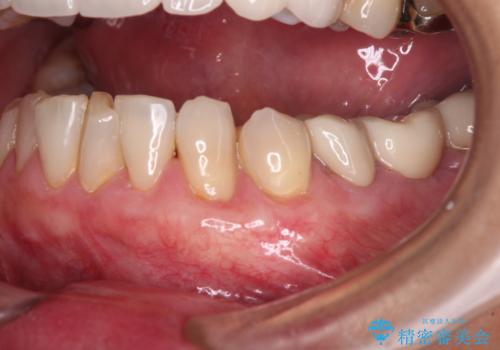

歯肉移植による根面被覆の結果、しみる症状は一切なくなりました。

歯肉の厚みが増したため、歯肉退縮のリスクが軽減されましたが、定期的に症状が再発していない確認していくことになります。